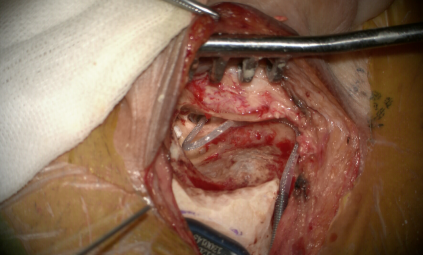

图片 2.png

磨圆窗龛,开放圆窗